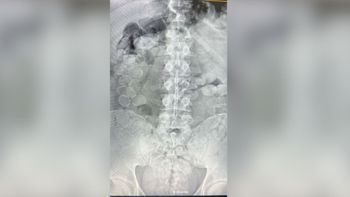

Después de que Gendarmería halló 105 kilos de cocaína y dos pasajeros con 160 cápsulas en el cuerpo en Ceres, un neurólogo detalló por qué una sola puede ser mortal.